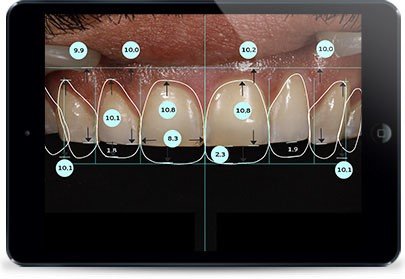

- Digital Smile Design Protocol

- Golden proportion assessment (ideal width-to-length ratio: 75-80%)

- Dental midline evaluation relative to facial midline (deviations <2mm generally acceptable)

- Gingival zenith positions and symmetry

- Incisal edge position and anterior guidance evaluation

2. Digital Smile Design Software

- 2D and 3D smile simulations

- Digital wax-up capabilities

- Precise proportion analysis

- Leading platforms: DSD App, Smile Designer Pro, exocad Smile Creator